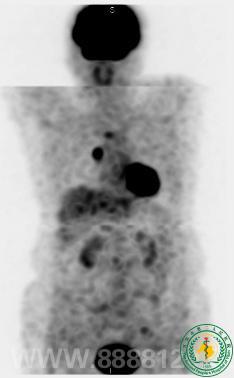

PET/CT发现一转移癌患者的隐匿性原发性肿瘤

PET/CT发现一转移癌患者的隐匿性原发性肿瘤7433